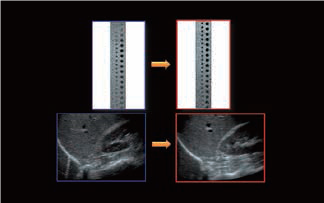

Малюнок 1. Технологія формування променя iBeam генерує клінічні зображення з вищою роздільною здатністю, більшою однорідністю та меншою кількістю артефактів, ніж звичайний промінь.

Малюнок 2. Інтелектуальна технологія динамічного мікро-зрізу (iDMS) забезпечує високу гнучкість електронного фокусування в лінзі та покращує роздільну здатність за глибиною.

Системи Canon Aplio™ i-серії розроблені для забезпечення неперевершеної візуалізації з покращеною роздільною здатністю та глибиною проникнення для підвищення клінічної точності, діагностичної ефективності та оптимізації часу роботи лікаря. Завдяки впровадженню вдосконаленої архітектури, технології формування пучка iBeam і технології інтелектуальних динамічних мікрозрізів (iDMS) можна формувати рівномірний, однорідний і тонкий зріз, який забезпечує клінічні зображення з вищою роздільною здатністю, більшою гомогенністю і меншою кількістю артефактів. Новітні технології забезпечують покращення контрастної, часової та просторової роздільної здатності у всіх трьох площинах: осьовій, бічній та глибині.